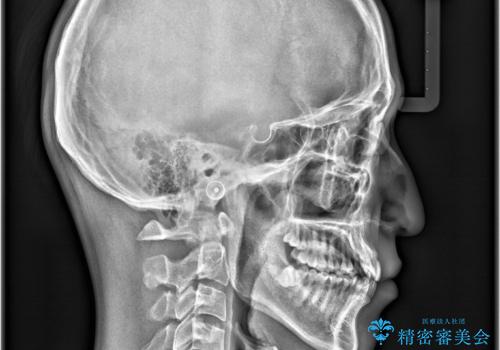

インビザラインで叢生の改善を行いました。

歯は抜かずに、拡大と少しのIPRで並べました。

矯正期間は半年です。